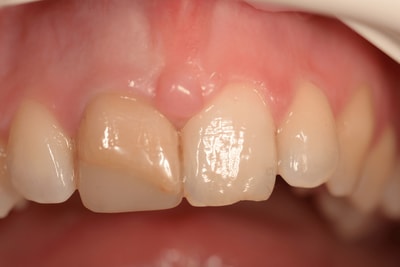

Situation Initiale

Cas terminé

Cas numero 2 :